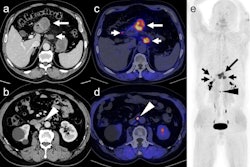

FAP is overexpressed by cancer cells, and research suggests it is an essential component driving the growth of tumors. When combined with medical isotopes such as gallium-68, radioligands that bind to FAP (radiotracers) have proven highly effective for visualizing cancer. FAP PET imaging has proven useful for initial staging, restaging, therapy response evaluation, and whole-body target expression assessment for therapy selection, the authors explained.

The guidelines outline several oncologic indications for FAP PET imaging, including gastrointestinal adenocarcinoma, pancreatic ductal adenocarcinoma, esophageal, head and neck cancer, thyroid, lung, and ovarian and breast cancers. In addition, it reviews the qualifications and responsibilities of imaging personnel and presents standardized quality control/quality assurance procedures and imaging procedures for FAP PET.